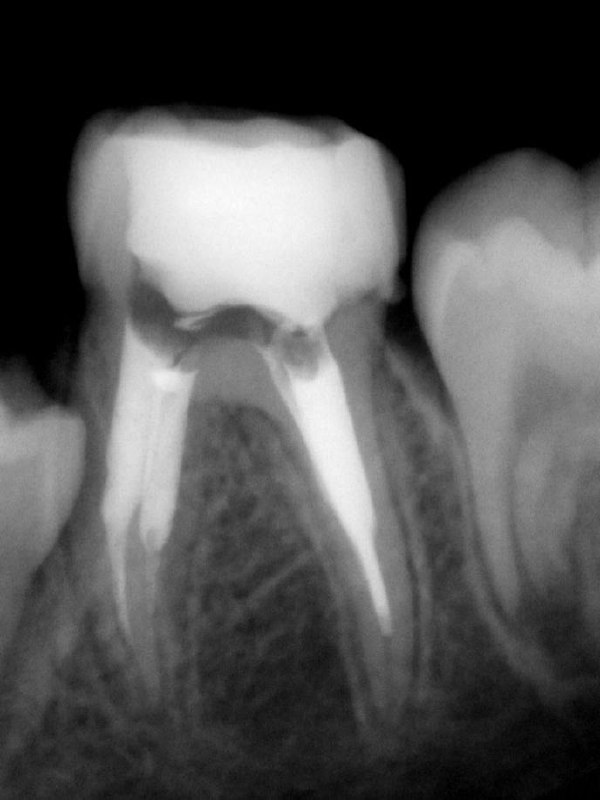

Клинический разбор: перфорация закрыта МТА, но боль сохранялась — причина в негомогенной обтурации и потребовалось перелечивание с разными методиками обтурации.